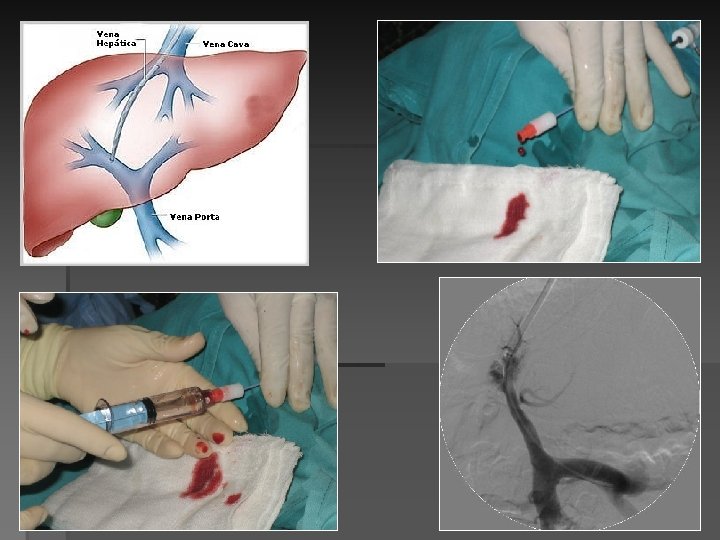

-V. hepática derecha la porta derecha está caudal y anterior. -V. hepática media la

-V. hepática derecha la porta derecha está caudal y anterior. -V. hepática media la porta derecha está caudal y posterior. -V. hepática izquierda la menos utilizada. Casos especiales. -V. porta derecha, bifurcación, porta izquierda, ramas segmentarias portales derechas.

-Medir gradiente portocava antes y tras el shunt. -Tras el TIPS descenso >50%, y

-Medir gradiente portocava antes y tras el shunt. -Tras el TIPS descenso >50%, y debe ser inferior a 12 mm Hg.

-Descenso del gradiente presión porto-sistémico. -Endovascular eco-Doppler (IVUS-Doppler) tras TIPS: aumento de velocidad pico

-Descenso del gradiente presión porto-sistémico. -Endovascular eco-Doppler (IVUS-Doppler) tras TIPS: aumento de velocidad pico sistólica y velocidad media arteria hepática indicadores de buena descompresión y funcionalidad del TIPS.